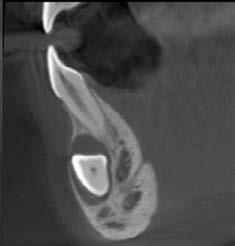

Oralchirurgie

Der Patient wurde zur chirurgischen Entfernung des mesial verlagerten impaktierten Weisheitszahns im rechten Unterkiefer überwiesen. Mit dem 3D R100 wurde ein DVT erstellt, um den Abstand zwischen Wurzel und Nerv zu bestimmen. Die sagittale und koronale Ansicht zeigten den Verlauf des rechten Mandibularkanals durch die Wurzeln des dritten Molaren im rechten Unterkiefer und die Verschmälerung der lingualen Kortikalisschicht.